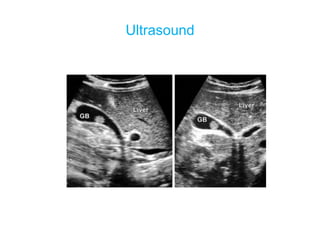

 Ultrasound abdomen—reveals presence or

absence of gallstones; and thickening of

gallbladder wall.

Ultrasound